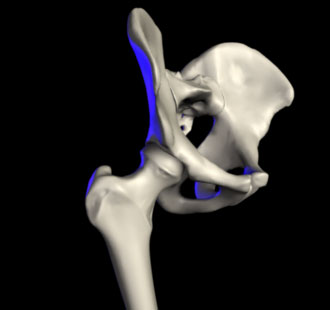

الردف أو الورك Hip منطقة من الجسم تقع بين الجذع والفخذ. ويتشكل مفصل الردف من عظم الردف الذي يتكون من ثلاثة عظام: عظم الحرقفة وعظم الإسك وعظم العانة، ومقدمة عظم الفخذ. وتتكيف مقدمة عظم الفخذ داخل الحُق، وهو تجويف في عظم الورك. ويشكل هذا النسق مفصلاً كرويًا حُقيًا، مما يعطي متانة كبيرة، ويسمح بمدى واسعٍ من الحركة في جميع الاتجاهات. وتحيط عضلات قوية عديدة بالمفصل، تتضمن العضلة الألوية الطرفية، وتكون عريضة ومستديرة في الخلف، والعضلة الألوية الوسطى في الجنب، والعضلة المستقيمة الفخذية الطويلة الشريطية في المقدمة. وتجعل هذه العضلات المفصل ثابتًا قويًا، بحيث يستطيع المرء أن يقف. وهي أيضًا تنقل الأرجل أثناء المشي والجري.

ويُولد العديد من الأطفال، وتجويفهم الوركي قليل العمق. ويطلق على هذه الحالة خلع الورك الولادي. وفي الأعمار المتقدمة، يُصبح عنق عظم الفخذ الذي يوجد أسفل مقدمة عظم الفخذ مباشرة، ضعيفًا، بحيث يسهل كسره. ويمكن إصلاح الكسر، بتثبيت رأس عظم الفخذ على العنق، بمسمار من الصلب المقاوم للصدأ. ويعاني كثير من ضحايا التهاب المفاصل، من ألم مُعجِز في مفصل الردف. وفي هذه الحالات، يمكن استبداله بحُق بلاستيكي وكرة معدنية بالمفصل.